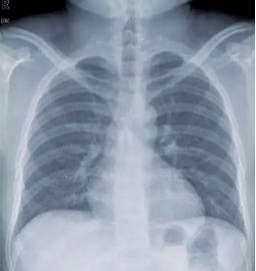

2025年9月,小东胸片显示:正常